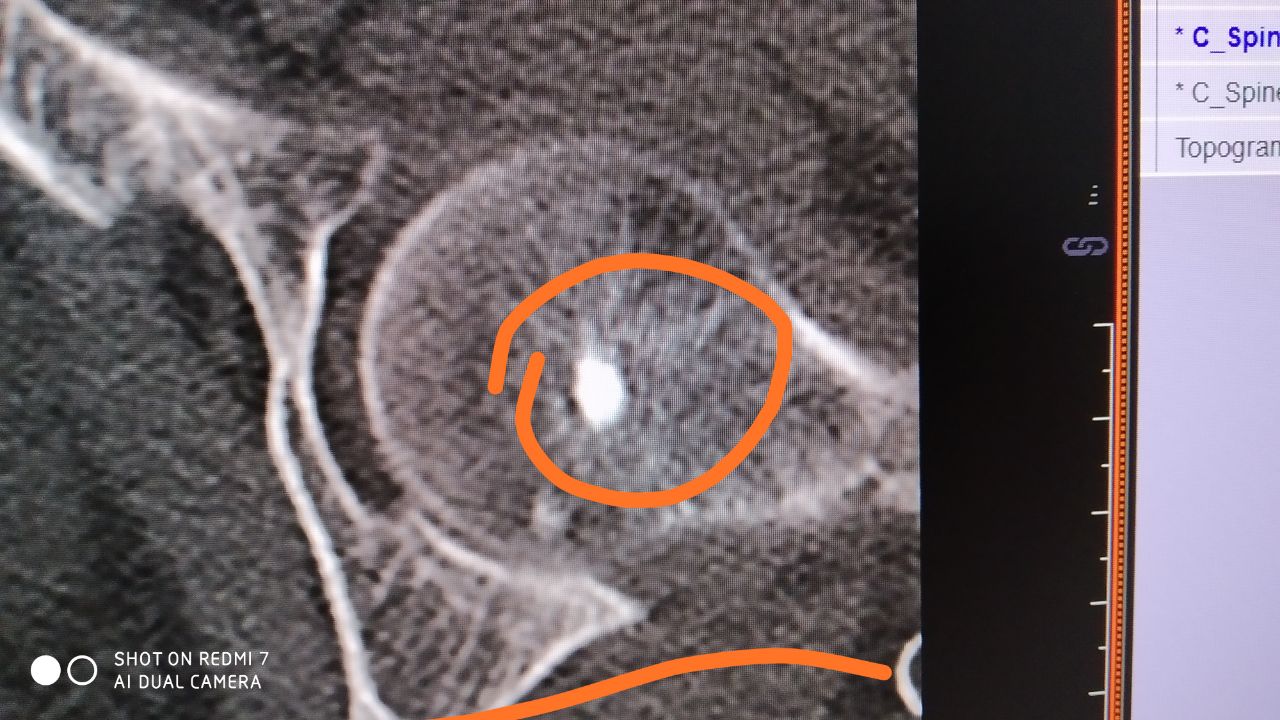

Жалобы на умеренные боли. Особенно когда сидит.. 68 лет.Женщина. Что видите?